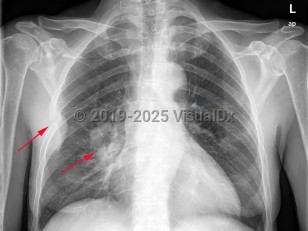

Lung cancer

Greater than 95% of lung cancers can be categorized as either small cell lung cancer (SCLC) or non-small cell lung cancer (NSCLC), with adenocarcinoma and squamous cell carcinoma being the most common NSCLC. Carcinoid tumors and mesothelioma may also arise in the lung but are less common. The lungs are also a common site of metastatic cancer.